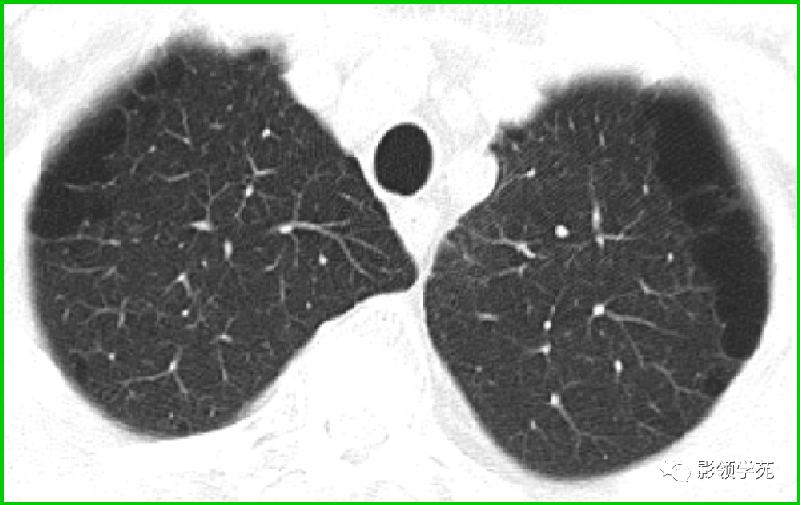

过敏性肺炎

马赛克征